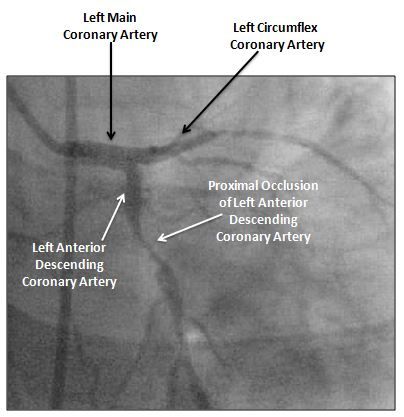

Figure 4. Coronary angiography prior to PCI, demonstrating proximal left anterior descending artery occlusion.

One such high-risk ECG pattern is termed “Wellens syndrome.”1-4 This high-risk ACS presentation is noted in patients with active or recent chest discomfort, precordial T-wave abnormalities (Figures 1, 2, and 3; please click to enlarge), and without ECG or biochemical evidence of acute myocardial infarction (MI). The high-risk nature is based on a very frequent association with proximal left anterior descending artery occlusion (LAD) (Figure 4; click to enlarge); this coronary lesion can progress over a very short period (hours to days) to anterior wall ST-segment elevation myocardial infarction (STEMI).1-4

The initial ED ECG (Figure 1) demonstrated prominent T-wave inversion in the precordial leads, a concerning finding. Despite the patient’s stable clinical presentation and pain-free state on ED arrival, the ECG was correctly recognized as high risk. Serial troponin values were normal; repeated ECGs did not demonstrate change. The patient remained sensation-free. Wellens syndrome was felt to be a likely issue. The patient was admitted to the cardiology service with coronary angiography performed later that day. A proximal LAD occlusion was noted (Figure 4) and successfully managed via intracoronary stent placement. The patient did well and was discharged from the hospital on day 2.